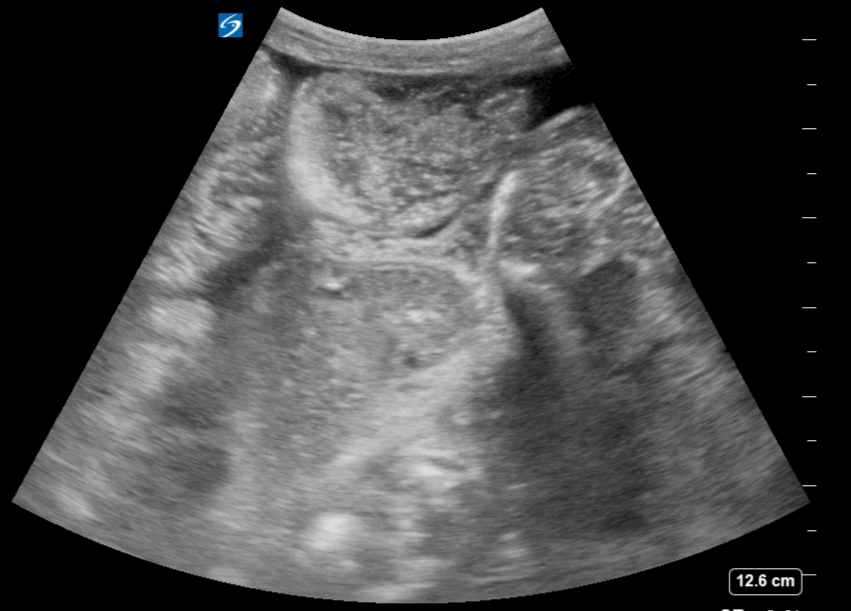

The video clip shows a small rim of free fluid along the liver edge with extensive free fluid noted amongst the intestinal loops

Free Fluid Around the Intestinal loops

Free Fluid in between the Intestinal loops